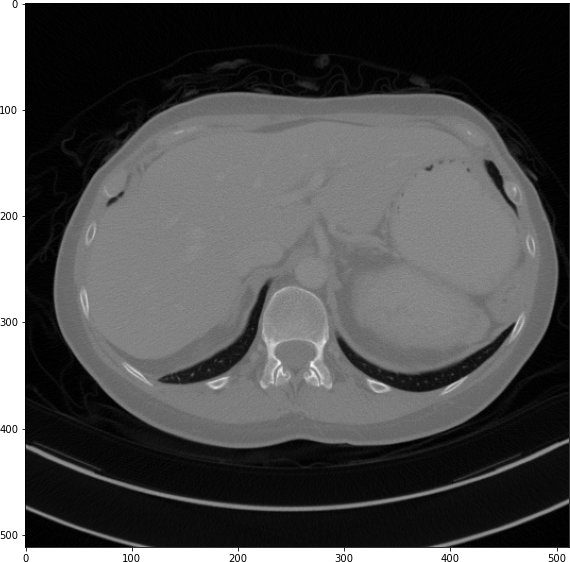

Refer to caption

(a) True Thick-slice image

(b) Simple Averaging

RMSE: 0.0329, PSNR: 35.6776

(c) Gaussian Averaging

RMSE: 0.0955, PSNR: 26.4221

(d) Direct Downsampling

RMSE: 0.0454, PSNR: 32.8776

(e) Proposed Simulation

RMSE: 0.0010, PSNR: 46.4076

Figure 2: Axial-plane thick-slice image quality comparison across four simulation methods.